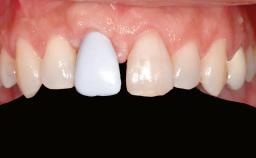

A 47-year-old Caucasian woman with a single-tooth edentulous space at the site of the left maxillary canine was referred for treatment. She had undergone traumatic extraction of this impacted canine several months before referral. Her chief complaint was the dissatisfying appearance of her smile. The patient desired a stable and esthetic rehabilitation of the site. Her dental history showed no evidence of periodontal disease or bruxism. She had no systemic diseases, was not taking any medications, and did not smoke. The extraoral examination revealed a high lip line and an inadequate soft-tissue volume at the defective canine site. Large black triangles were visible between the canine and its adjacent teeth.

Lip Line No exposure of papillae Exposure of papillae Full exposure of mucosa margin

Periodontal Phenotype Low-scalloped, thick Medium-scalloped, medium-thick High-scalloped, thin

Shape of Tooth Crowns Rectangular Triangular

Soft Tissue Anatomy Intact Defective